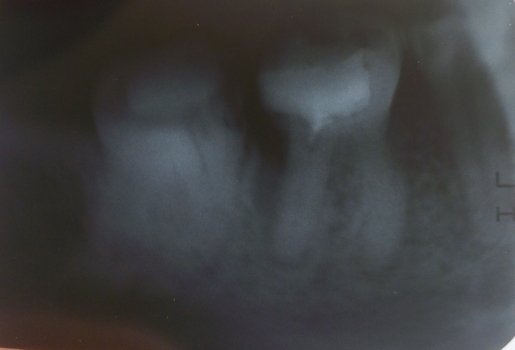

В подростковом возрасте мне сделали резекцию передних зубов из-за кисты. Но спустя примерно 15 лет над зубом образовался, на ощупь, шарик и очень неприятное напряжение под зубом. Я пошла к врачу, он отправил на снимок, но так и не смог мне помочь, и отправил к другому стоматологу, но попасть к нему я так и не смогла.

Вы не могли бы мне сказать, что это? И к кому мне нужно обратиться? У нас городок маленький и специалистов не так много.

У вас так называемый рецидив. Обратитесь к хирургу, думаю, данный зуб придется удалить.